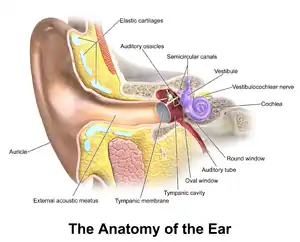

In the anatomy of humans and various other tetrapods, the eardrum, also called the tympanic membrane or myringa, is a thin, cone-shaped membrane that separates the external ear from the middle ear. Its function is to transmit sound from the air to the ossicles inside the middle ear, and then to the oval window in the fluid-filled cochlea. Hence, it ultimately converts and amplifies vibration in the air to vibration in cochlear fluid.[1] The malleus bone bridges the gap between the eardrum and the other ossicles.[2]

Orientation and relations

The tympanic membrane is oriented obliquely in the anteroposterior, mediolateral, and superoinferior planes. Consequently, its superoposterior end lies lateral to its anteroinferior end.

Anatomically, it relates superiorly to the middle cranial fossa, posteriorly to the ossicles and facial nerve, inferiorly to the parotid gland, and anteriorly to the temporomandibular joint.

Regions

The eardrum is divided into two general regions: the pars flaccida and the pars tensa.[3] The relatively fragile pars flaccida lies above the lateral process of the malleus between the Notch of Rivinus and the anterior and posterior malleal folds. Consisting of two layers and appearing slightly pinkish in hue, it is associated with Eustachian tube dysfunction and cholesteatomas.[4]

The larger pars tensa consists of three layers: skin, fibrous tissue, and mucosa. Its thick periphery forms a fibrocartilaginous ring called the annulus tympanicus or Gerlach's ligament.[5] while the central umbo tents inward at the level of the tip of malleus. The middle fibrous layer, containing radial, circular, and parabolic fibers, encloses the handle of malleus. Though comparatively robust, the pars tensa is the region more commonly associated with perforations.[6]

Umbo

The manubrium (Latin: handle) of the malleus is firmly attached to the medial surface of the membrane as far as its center, drawing it toward the tympanic cavity. The lateral surface of the membrane is thus concave. The most depressed aspect of this concavity is termed the umbo (Latin: shield boss).[7]